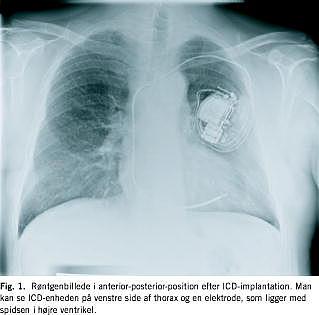

En implanterbar cardioverter defibrillator (ICD) er en særlig avanceret pacemaker, som kan foretage kardiovertering (afbryde ventrikulær takykardi med elektrisk stød), defibrillering (afbryde ventrikelflimren med elektrisk stød) eller takykardibrydende pacing ved ventrikulære takyarytmier og konventionel pacing ved bradyarytmier [1]. Enheden placeres subkutant eller submuskulært på thorax, og en særlig defibrilleringselektrode føres transvenøst til højre ventrikels apex (Fig. 1 ). Den perioperative mortalitet er minimal. Implantationen kan kompliceres af hæmatom, pneumothorax og elektrodedisplacering og på længere sigt af infektion og utilsigtet terapi. ICD-enheden holder i seks år, elektroderne holder betydeligt længere.